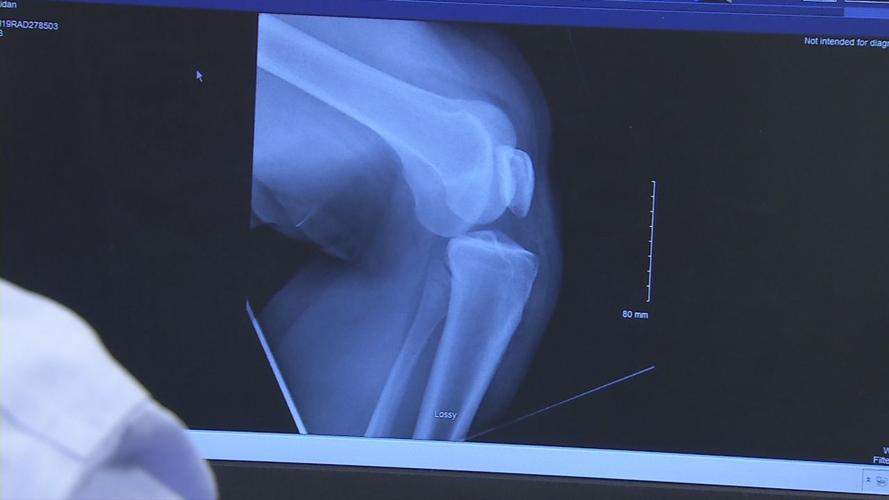

Meanwhile, injuries from trampolines are causing a jump in cases for doctors in the Louisville area. Norton Children's Orthopedics of Louisville treats trampoline injuries daily. Recently Dr. Josh Meier referred to an X-ray as he explained a knee injury he treated.

"The kneecap is out of position," Meier said. "The entire knee is dislocated. This was a trampoline injury."